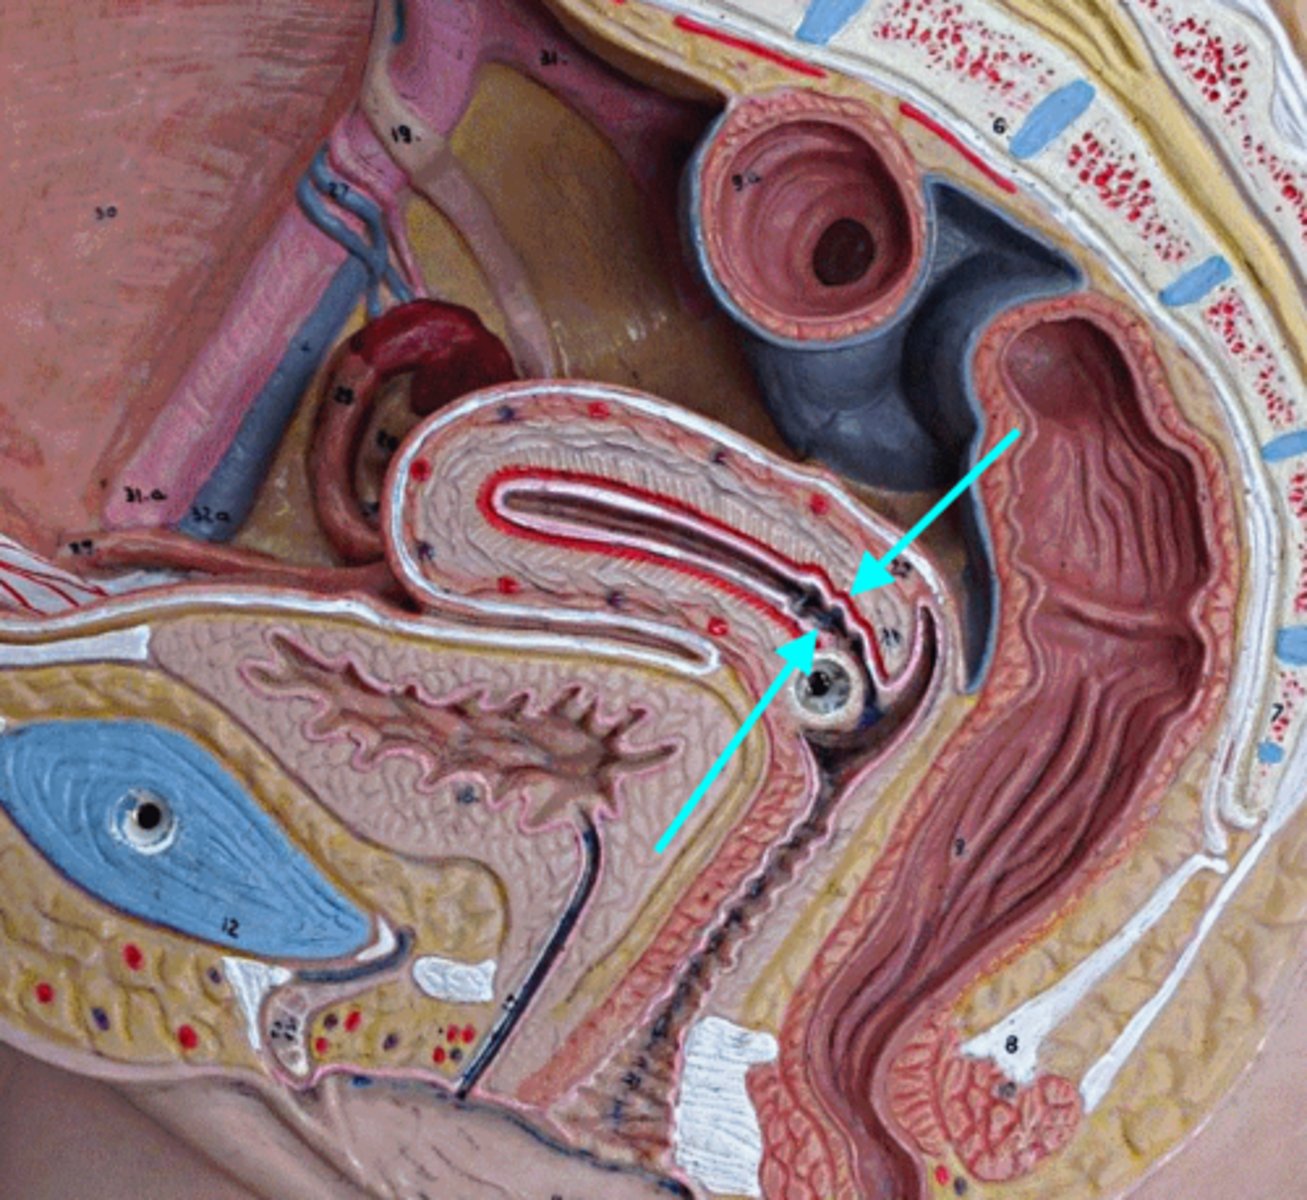

Vagina

Vaginal orifice

Hymen

Vaginal fornix

Cervix

Internal os

Cervical canal

External os